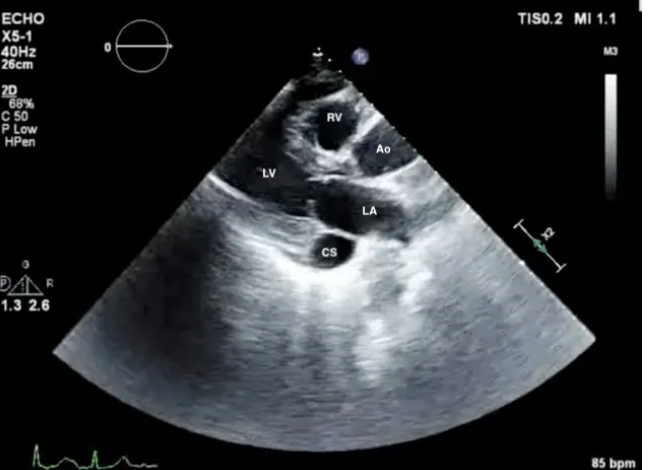

The arrow in the following image is pointing to the:

A

coronary sinus

*PLAX view showing dilated coronary sinus, raising suspicion for persistent left SVC